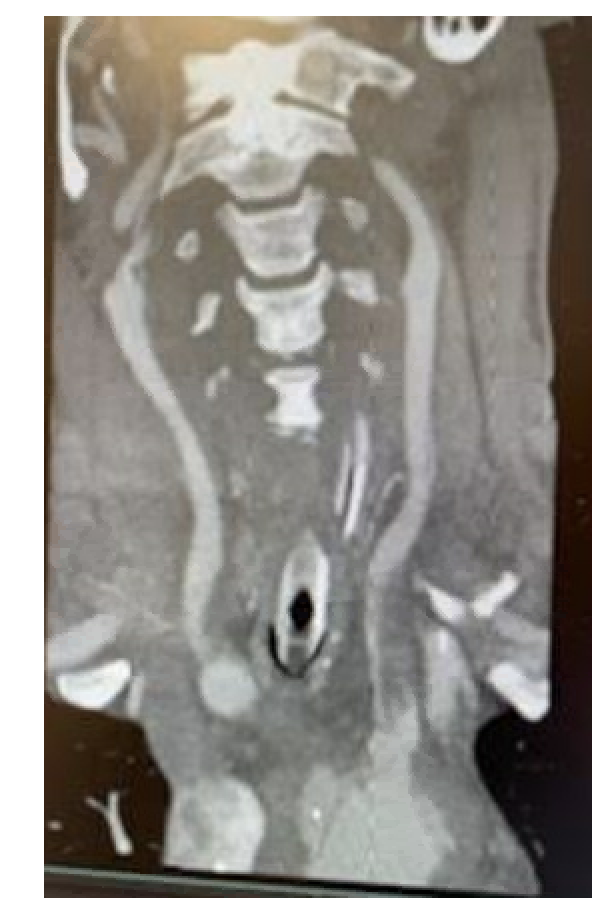

Postoperatively, the patient was noted to have left-sided weakness and a markedly decreased level of consciousness (LOC). There was no evidence of stroke or intracranial hemorrhage on head computed tomography (CT). A head and neck CT angiogram demonstrated near total effacement of the true lumen of the left CCA (Figure 1) and 60% stenosis of the mid-right CCA from a dissection flap involving the vessels (Figure 2).